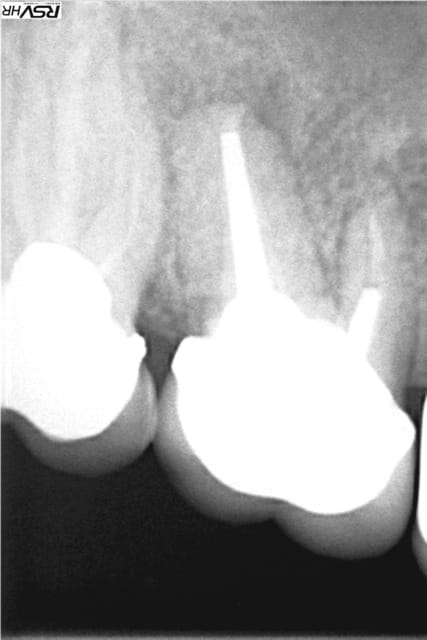

même si je me redirige plutôt vers Zimmer avec une insertion primaire supérieur (à mon avis ) voici un cas de plusieurs années

j'avais gardé une racine distale de 46 (montage 2 ccm soudées au début 4647- avec diastème avec 45 ;2008;le montage

n'a pas tenu longtemps=extraction racine distale et

implantation immédiate legacy2 7 mm(2011)

et ccm transvissée 3 mois après

radio à 2015